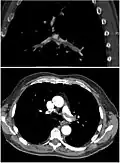

Ventilation/perfusion scan

(A) After inhalation of 20 mCi of Xenon-133 gas, scintigraphic images were obtained in the posterior projection, showing uniform ventilation to lungs.

(B) After intravenous injection of 4 mCi of Technetium-99m-labeled albumin, scintigraphic images are shown here in the posterior projection. This and other views showed decreased activity in multiple regions.

A ventilation/perfusion scan (or V/Q scan or lung scintigraphy) shows that some areas of the lung are being ventilated but not perfused with blood (due to obstruction by a clot).[19] This type of examination is as accurate as multislice CT, but is less used, due to the greater availability of CT technology. It is particularly useful in people who have an allergy to iodinated contrast, impaired kidney function, or are pregnant (due to its lower radiation exposure as compared to CT).[66][67][68] The test can be performed with planar two-dimensional imaging, or single-photon emission computed tomography (SPECT) which enables three-dimensional imaging.[59] Hybrid devices combining SPECT and CT (SPECT/CT) further enable anatomic characterization of any abnormality.[69]